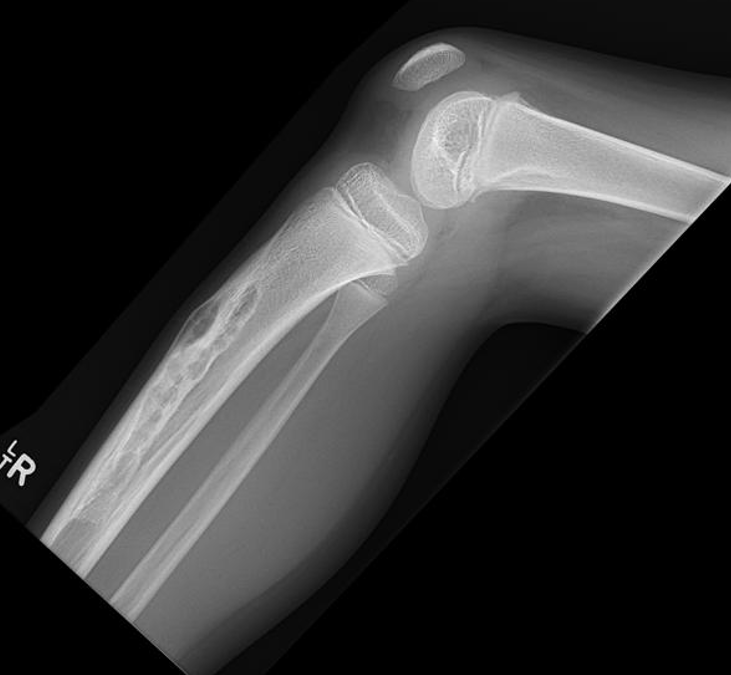

X-ray

Multiple small radiolucent lesions surrounded by sclerosis

Thickened cortex

Doesn't progress on xray